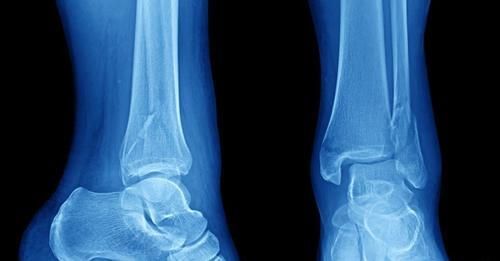

1、骨刺

文章插图

骨刺其实就是我们骨质增生比较严重,有些关节受到压迫软骨织磨损后自我修复出现增生的情况,这是人体衰老的正常现象之一。从某种方面来讲,骨质增生甚至可以看作是我们人体的自我恢复系统运转的结果,只有在骨质增生非常严重影响到我们日常生活,或者造成其他并发症的时候才需要进行治疗。